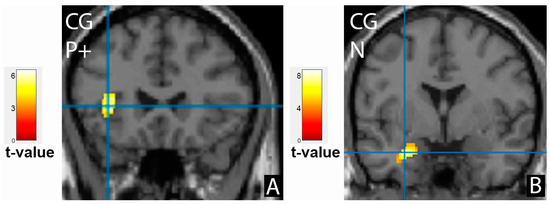

3.3. Comparison of Brain Activation Patterns in Patients before Treatment and Healthy Controls

| Cluster Location | Emotion | Extent | t-Value | p (FWE Corrected) | MNI Coordinates |

|---|---|---|---|---|---|

| Control group, cortical activation | |||||

| Frontal cortex | |||||

| Right inferior frontal gyrus | P+ | 280 | 7.29 | 0.041 | 46;36;8 |

| Left inferior frontal gyrus, insula | P+ | 358 | 5.93 | 0.014 | −36;24;4 |

| Control group, cortical deactivation | |||||

| Right limbic lobe, cingulate gyrus, precuneus | N | 2851 | 9.49 | <0.001 | 6;−56;28 |

| Left limbic lobe, cingulate gyrus, BA31, precuneus | N- | 159 | 4.93 | 0.043 | −10;−58;24 |

| Left limbic lobe, cingulate gyrus, BA23 | P+ | 143 | 4.61 | 0.072 | −2;−36;30 |